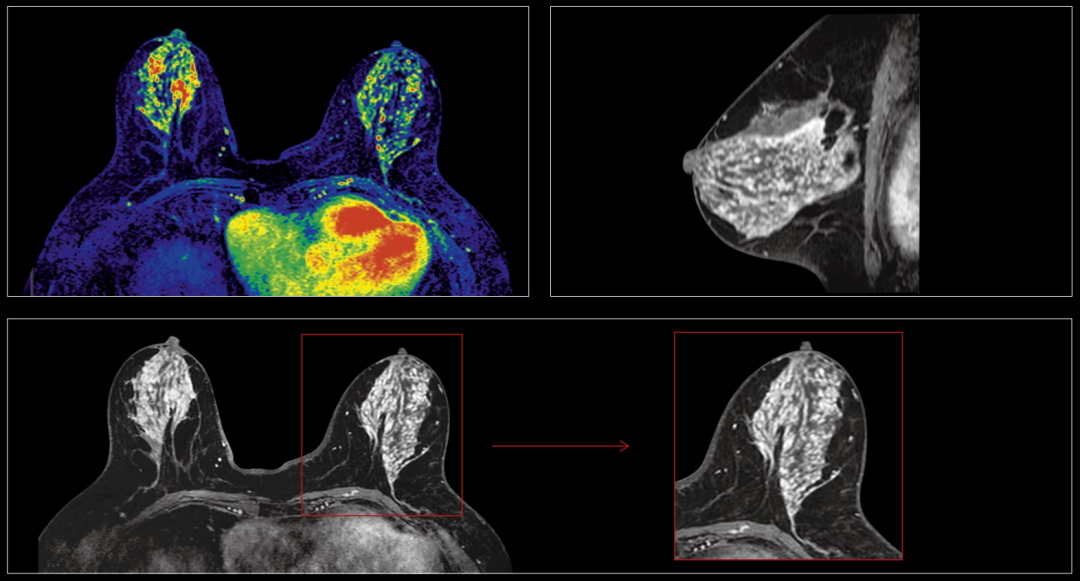

6、全身软组织病变:

无论来源于神经、血管、淋巴管、肌肉、结缔组织的肿瘤、感染、变性病变等,皆可做出较为准确的定位、定性的诊断。

联影磁共振怎么样【三级医院创建 • 技术装备提升】再添医学影像“利器”——我院引进联影uMR870  3.0T磁共振_https://www.jmylbn.com_新闻资讯_第25张

肾上腺常规成像

联影磁共振怎么样【三级医院创建 • 技术装备提升】再添医学影像“利器”——我院引进联影uMR870  3.0T磁共振_https://www.jmylbn.com_新闻资讯_第26张

乳腺常规动态增强